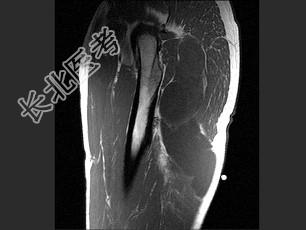

- 单项选择题女,47岁, 足部疼痛,运动员, 结合图像,最可能的诊断是 ( )

A、肌内黏液瘤

B、脂肪瘤

C、血管瘤

D、肌内脓肿

E、滑膜肉瘤